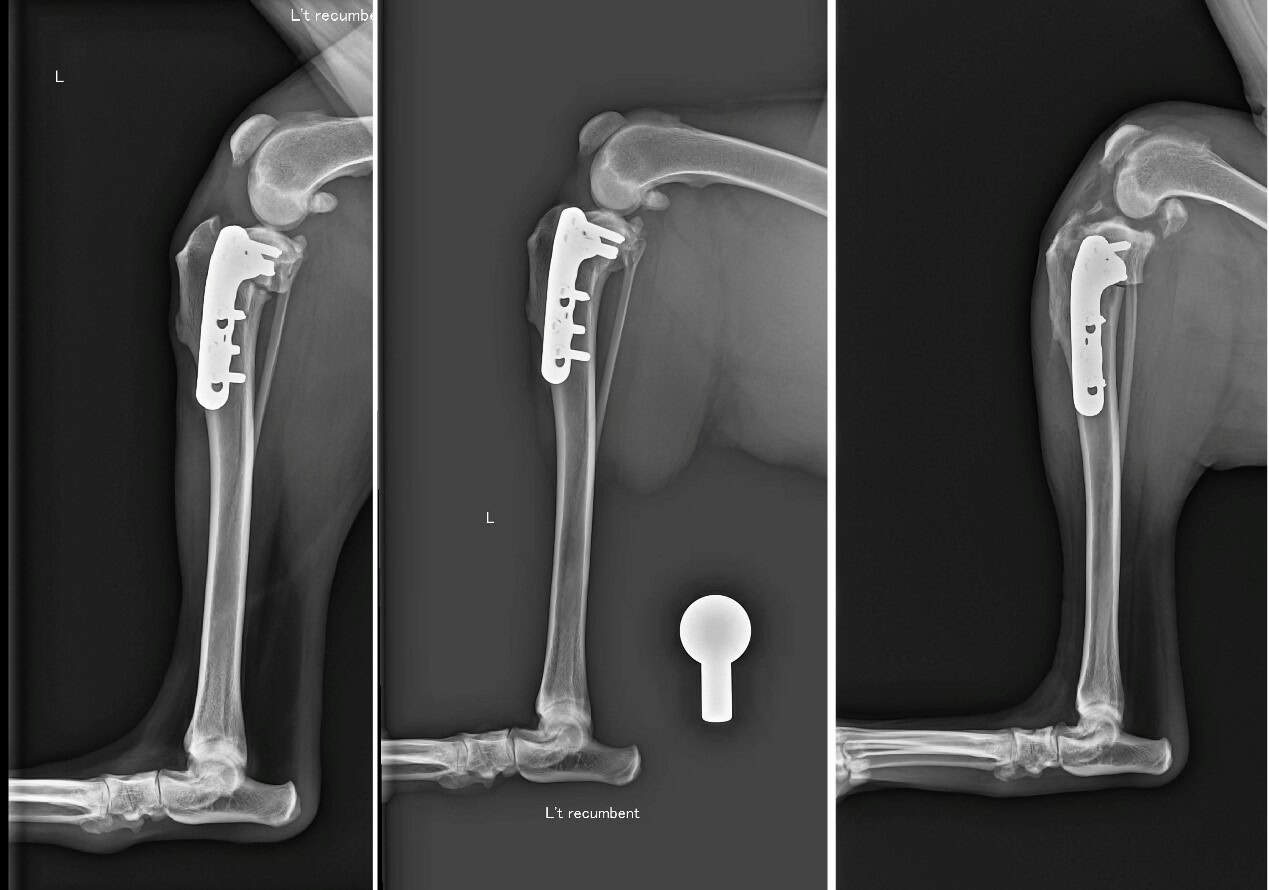

TPLO (Tibial Plateau Leveling Osteotomy) 是目前國際公認治療前十字韌帶斷裂的黃金標準手術。

它的原理非常巧妙: 既然韌帶斷了,我們不再執著於修補那條脆弱的韌帶,而是透過幾何力學的改變,將脛骨切開並旋轉角度,改變膝關節受力的平臺。術後,狗狗的膝蓋不再需要依靠前十字韌帶就能在行走時保持穩定。